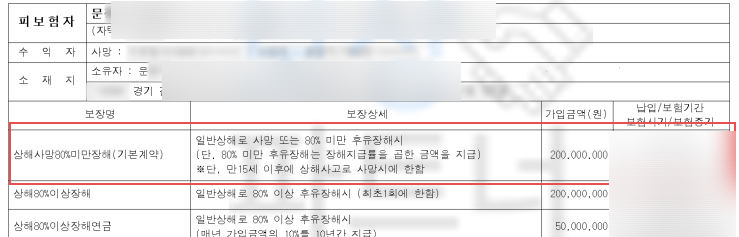

의뢰인의 보험 증권을 분석한 후 보상의 가능성을 확인하게 되었고 저희는 후유장해보험금 청구를 위임받게 되었습니다.

해당하는 장해를 진단받았죠. 저희는 의뢰인의 장해를 보험사에 서류로 증명할 수 있는 손해사정서와 관련 증빙자료를 추가적으로 제출했고 물론 보험사와 약 한 달간 분쟁이 오가며 각종 의료 자문, 심사를 진행했지만!

결국 저희가 처음 청구한 지급률 5% 영구 장해 모두 인정되어!

후유장해보험금 1,500만 원